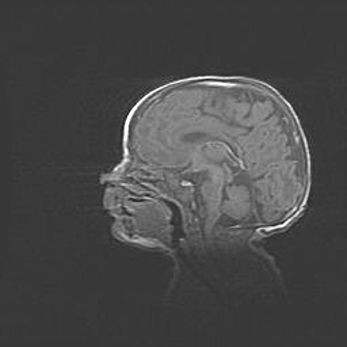

Аномалия Денди-Уокера. Признаки гипоплазии мозолистого тела.

Возраст: 5 месяцев 3 дня

Вес: 5550 г

Пол: мужской

Окружность головы: 39 см

Срок гестации: 40 недель

Аномалия Денди-Уокера – это порок развития головного мозга, для которого характерна триада симптомов: гипотрофия или аплазия червя мозжечка и/или полушарий мозжечка, расширение четвёртого желудочка с формированием ликворной кисты задней черепной ямки, гипертензионная гидроцефалия различной степени.

Гипоплазия мозолистого тела относится к дефектам внутриутробного этапа развития мозговой ткани, возникающим в процессе закладки структур головного мозга, что происходит на начальных этапах развития эмбриона.